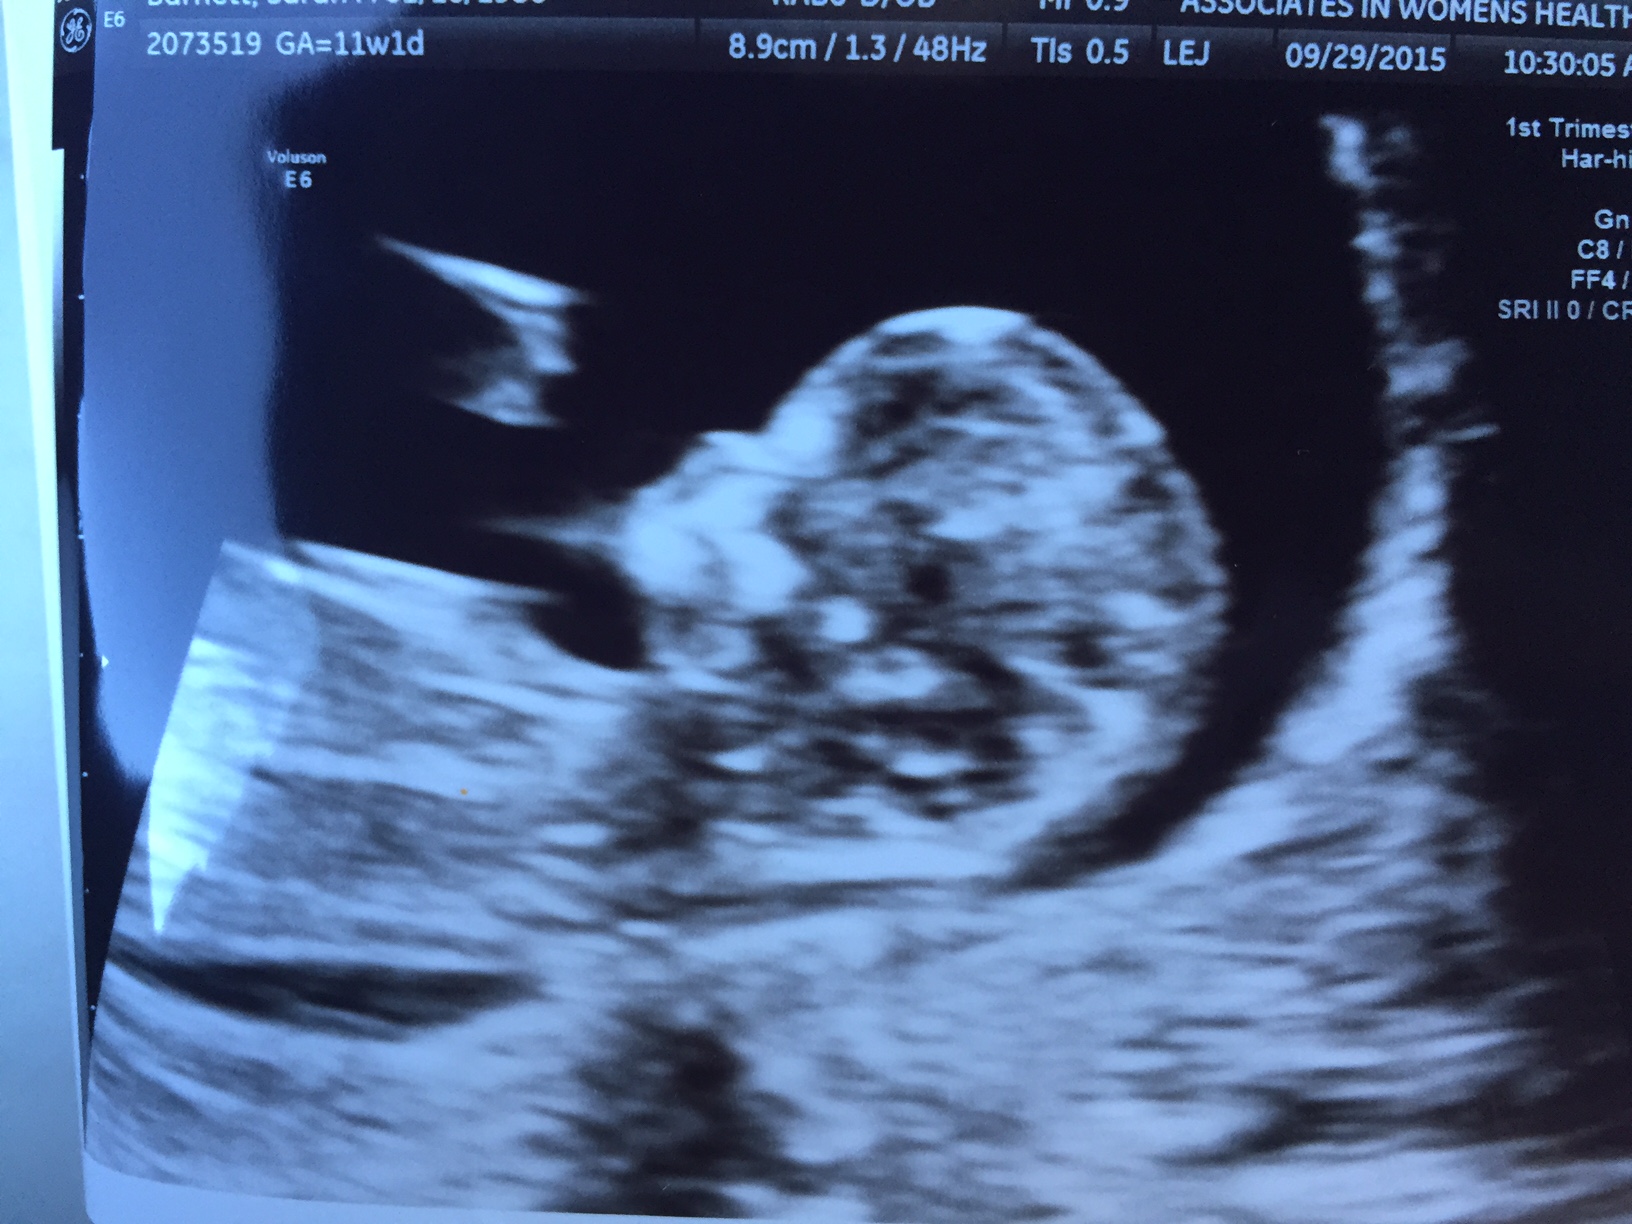

Hi! I've been waiting for this ultrasound for forever it seems like. This was at 11w1d. The ultrasound tech was happy to give me a nub shot and her own guess, too. I also included a skull pic for skull theory. Let me know what you think! I swayed girl, and have two beautiful boys I adore. We are happy with whoever this LO is!!

Attachment 27613Attachment 27612